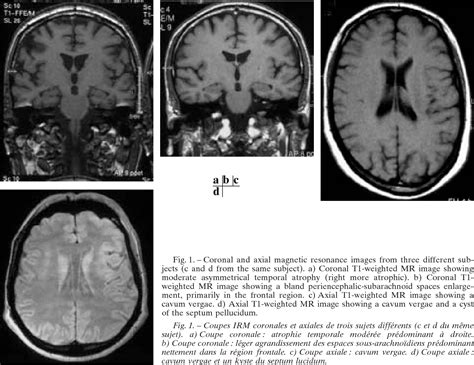

The Kip Kinkel brain scan was conducted as part of a broader effort to understand the neurological basis of violent behavior. The scan revealed several abnormalities in Kinkel's brain, particularly in areas associated with impulse control, emotion regulation, and decision-making. These findings have been pivotal in advancing the field of forensic neuroscience, offering a glimpse into how neurological factors might contribute to violent acts.

One of the key findings from the Kip Kinkel brain scan was the presence of reduced activity in the prefrontal cortex, a region of the brain crucial for executive functions such as impulse control and decision-making. This area is often referred to as the brain's "control center," and its dysfunction can lead to impulsive and aggressive behavior. Additionally, the scan showed abnormalities in the amygdala, a region involved in processing emotions, particularly fear and aggression.

These neurological abnormalities suggest that Kinkel may have had difficulty regulating his emotions and controlling his impulses, factors that could have contributed to his violent actions. However, it is important to note that neurological findings alone do not explain complex behaviors like school shootings. Environmental, psychological, and social factors also play significant roles.